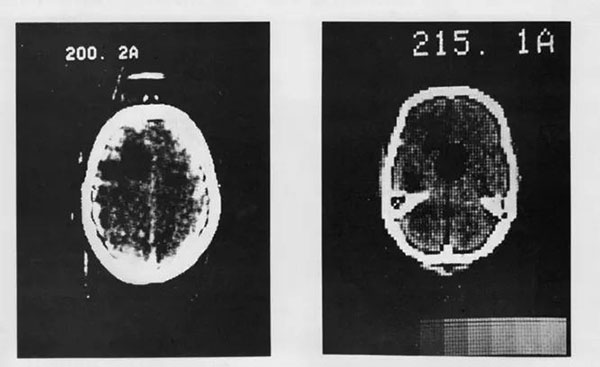

Исследователи установили полномасштабный сканер в лондонской больнице Аткинсона Морли, и 1 октября 1971 года под руководством Амброуза было проведено первое сканирование мозга реального пациента. Это была женщина среднего возраста с подозрением на кисту головного мозга неизвестной локализации.

Изначально первая модель томографа не была оснащена компьютером для обработки изображений. Процесс обработки данных занимал много времени: полчаса ушло на само сканирование, затем Хаунсфилд отвез магнитные ленты с данными в офис компании EMI, где обработка заняла ещё 2,5 часа. После этого изображения были получены с помощью фотоаппарата Polaroid и возвращены в больницу.

Амброуз вспоминал, что сканирование позволило чётко определить местоположение кисты. Когда снимки были готовы, они с Хаунсфилдом почувствовали себя как игроки, забившие победный гол.

Первая презентация предварительных клинических данных состоялась на конференции Британского института радиологии 20 апреля 1972 года, к этому времени было обследовано около 70 пациентов. Опубликованные результаты произвели фурор в области медицинской рентгеновской техники со времён открытия рентгеновских лучей. Компьютерная томография быстро стала новым стандартом в развитии медицинской рентгеновской техники.